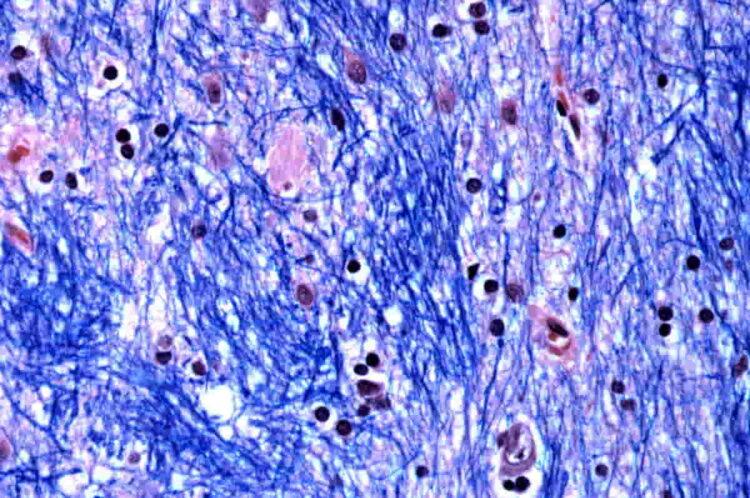

The research, conducted by scientists at the Broad Institute of MIT and Harvard, McLean Hospital, and Harvard Medical School, analyzed brain tissue from 53 individuals with Huntington’s and 50 without it. The team focused on the gene mutation, which involves a repeated three-letter DNA sequence, CAG.